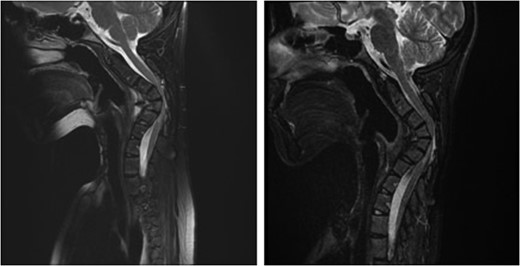

Sagittal (left) and axial (right) T1-weighted contrast-enhanced magnetic resonance images before the second surgery, showed increased size of the extraspinal component of the tumor, with kyphotic deformity of the cervical spine.